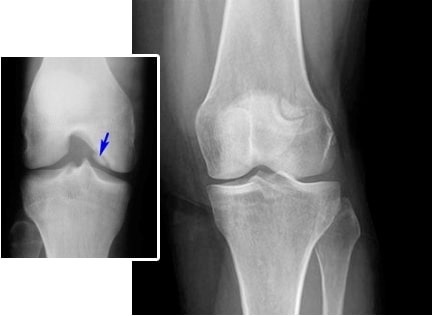

Liječenje zglobova lakta. Žena. 31 godina. Trajanje liječenja: 2 mjeseca. Hrskvica se potpuno oporavila: